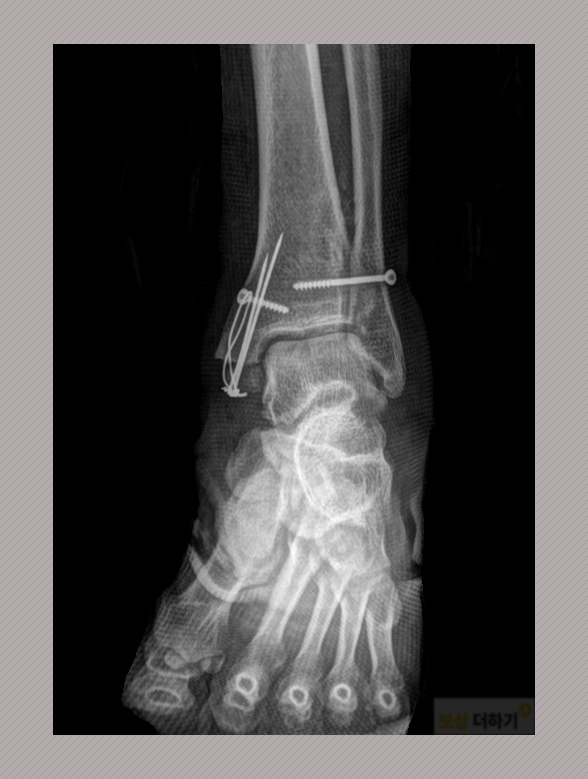

▷ 진단명 : 좌측 발목 경골 하단 골절 (S82.380) 좌측 비골 경부 골절 경골 하단의 경우에는 뼈의 어긋난 정도가 심각해서 수술적인 치료가 필요한 상황이었습니다.

관혈적 정복 및 내 고정술 시행 받으시고 이후에는 부목 고정을 하였습니다. 한동안 목발을 이용하시면서 보존적인 치료를 계속하셨는데요. 몇 달 동안 고정된 상태에 있다 보니 관절의 강직 현상이 자연히 따라오게 되었죠.